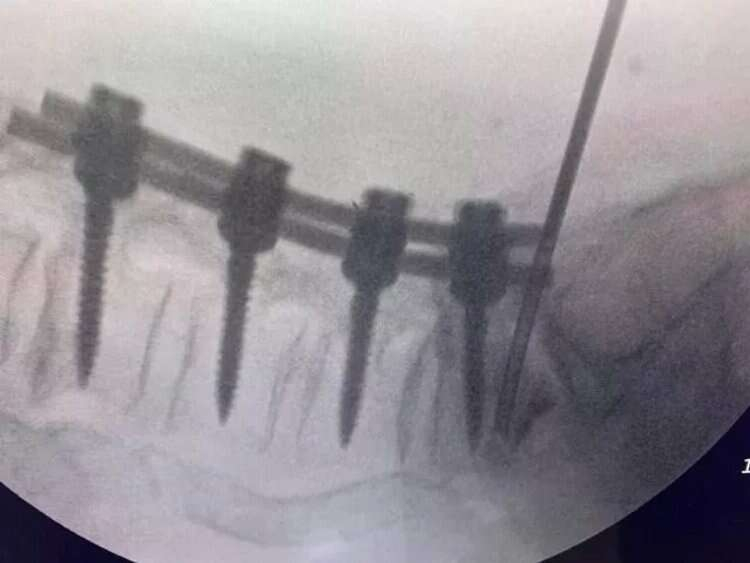

Hekimler; kırıklar, skolyoz eğrilikleri, tümörler, kanal daralması gibi ameliyatlarında vidalarla omurları desteklemede bulunuyor. Ancak vidaların bulunduğu omurlar düşme, çarpma gibi kazalar nedeniyle kırılabiliyor. Bu duruma müdahale etmek için ise açık ameliyat gerekiyor. Beyin ve Sinir Cerrahisi Uzmanı Prof. Dr. Kemal Yücesoy, vidalı omurganın kırığına dünyada ilk kez transforaminal transdiskal yaklaşımla sement desteği yaptı.

Uzun süre, vidayı çıkarmadan kemik çimentosunu koyma konusunda çalışmalar yaptığını belirten Prof. Dr. Yücesoy, “Kapalı bel fıtığı ameliyatlarında iğneyle sinirin altına girerek izlediğimiz bir yol var. ‘Hastaların kemiğinin içine bu yoldan girilebilir’ diye düşündüm ve bunu da uygulamaya başladım. Bu yöntemde, hastaya lokal anestezi uyguluyoruz. Kıkırdağın olduğu bölümden diskin içine iğneyle girip oradan da kemiğin içine ulaşıyoruz ve çimentoyu koyuyoruz. Bu daha önce hiç uygulanmamış bir yol. Kırılmış vidalı bir kemiğe ilk kez o vidayı çıkarmadan kapalı yöntemle girip müdahale etmiş olduk” diye konuştu.